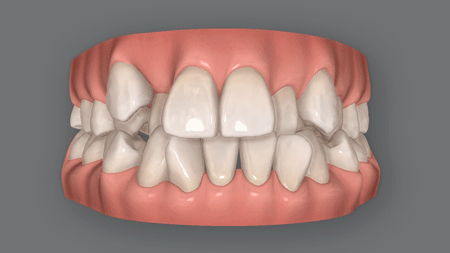

受け口とは?

反対咬合下顎前突(かがくぜんとつ)とも呼ばれる受け口は、下の前歯が上の前歯より前方に飛び出している症状。

横から見ると下顎が突き出して見えることから、「しゃくれ」、あるいは「三日月顔」と形容されることもあります。